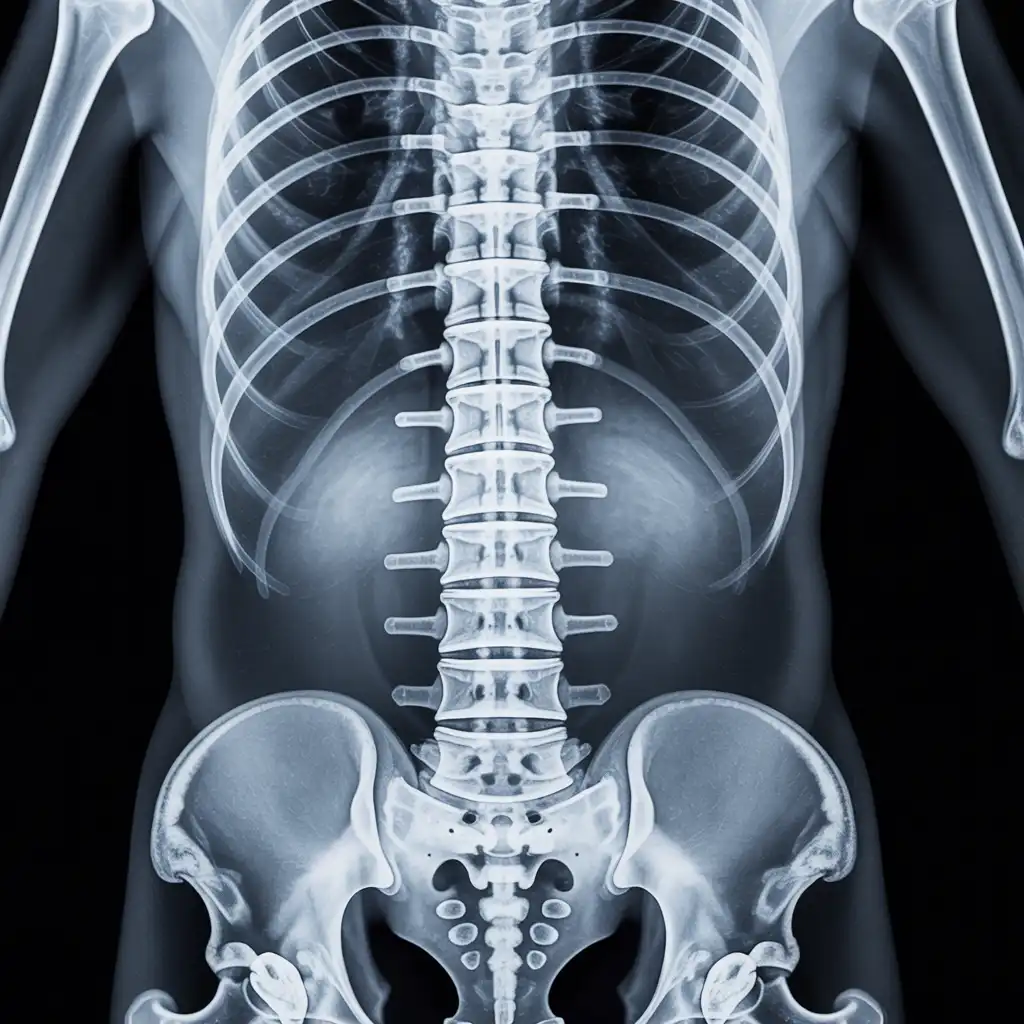

Da anni offriamo un servizio di radiografie a domicilio pensato per garantire ai nostri pazienti la stessa qualità diagnostica degli esami eseguiti in ospedale, ma con la comodità e la sicurezza della propria casa.

Abbiamo effettuato migliaia di esami direttamente presso abitazioni, residenze e strutture assistenziali, utilizzando apparecchiature digitali portatili certificate e procedure rapide e sicure.